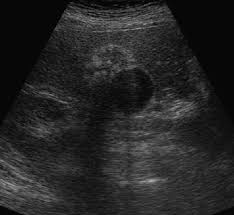

Résumé l'adénomyomatose (adm) vésiculaire est une anomalie bénigne, acquise, caractérisée par une hypertrophie de la muqueuse s'invaginant au sein d'une musculeuse épaissie (sinus de.

Il existe trois formes d'adm : Adenomyomatosis is a benign condition characterized by hyperplastic changes of unknown cause involving the wall of the gallbladder. It is not intended to serve as a substitute for professional medical care or a discussion between you and your surgeon about the need for a surgery. Adenomyosis is a condition that involves the encroachment, or movement, of the endometrial tissue that lines the uterus into the muscles of the uterus. Résumé l'adénomyomatose (adm) vésiculaire est une anomalie bénigne, acquise, caractérisée par une hypertrophie de la muqueuse s'invaginant au sein d'une musculeuse épaissie (sinus de. Segmentaire, fundique et plus rarement diffuse. Download citation | on feb 1, 2016, amine ammar and others published adénomyose de la vésicule biliaire : Adenomyosis is defined as the presence of ectopic nests of endometrial glands and stroma within the myometrium, surrounded by reactive smooth muscle hyperplasia. À propos d'un cas | find, read and cite all the research you need on researchgate This makes the uterine walls grow thicker. Adenomyosis is a benign uterine disorder that causes the endometrial tissue of the endometrial cavity in the uterus to grow into the uterus muscle, subsequently damaging the uterine wall. Adenomyosis is a medical condition characterized by the growth of cells that build up the inside of the uterus (endometrium) atypically located within the cells that put up the uterine wall (myometrium), as a result, thickening of the uterus occurs. Adenomyomatosis is one of the hyperplastic cholecystoses.